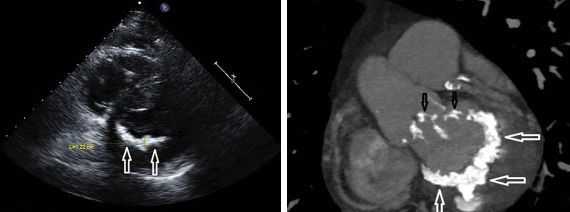

При аускультации голосистолический шум лучше всего выслушивается па верхушке сердца и иррадиирует в левую подмышечную область. Наиболее достоверным диагностическим исследованием является цветная допплер-эхокардиография, особенно чреспищеводная эхокардиография, которые позволяют получить точное изображение регургигирующей струи и количественные данные о пей. При помощи эхокардиографии можно также установить, какая именно аномалия митрального клапана вызывает регургитацию.

Другой важный инструментальный метод диагностики — эхокардиография (Эхо-КГ) . Эхо-КГ — это безболезненное ультразвуковое исследование, которое позволяет исследовать работу сердца в реальном времени. Эхокардиография покажет уменьшение эластичности клапана, его повреждение, размер отверстия митрального клапана и расстояние между его створками. Также при исследовании можно увидеть разрыв папиллярной мышцы и провисание клапанных створок в полость левого предсердия [4] [8] [9] .